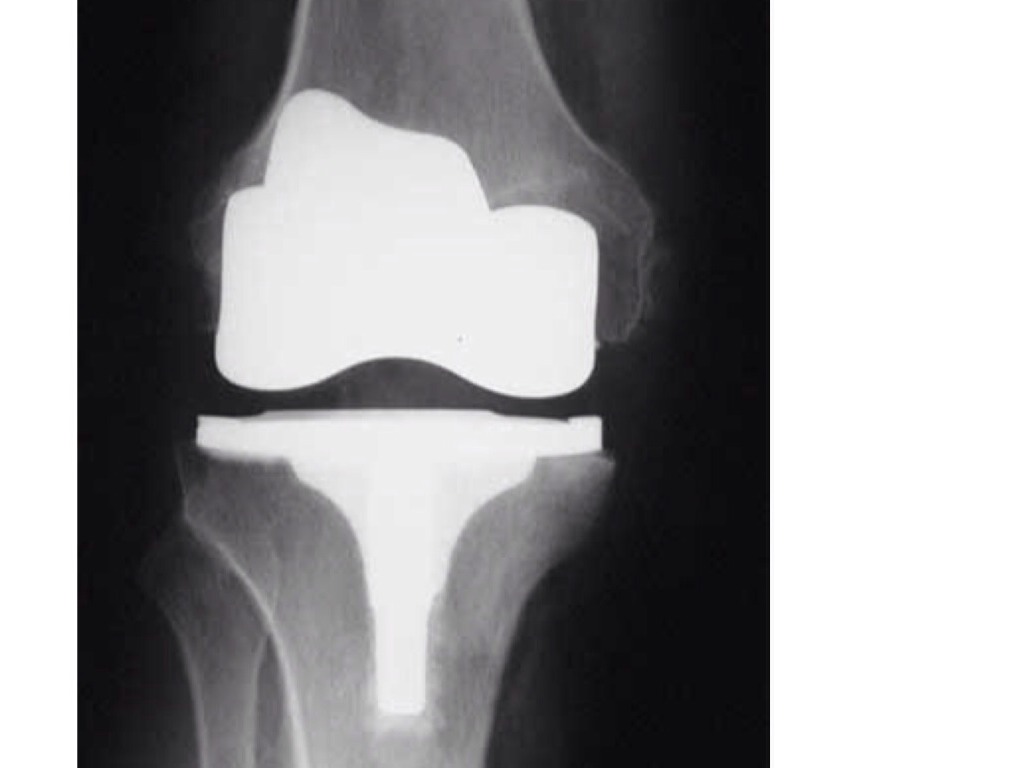

Man steals ring!